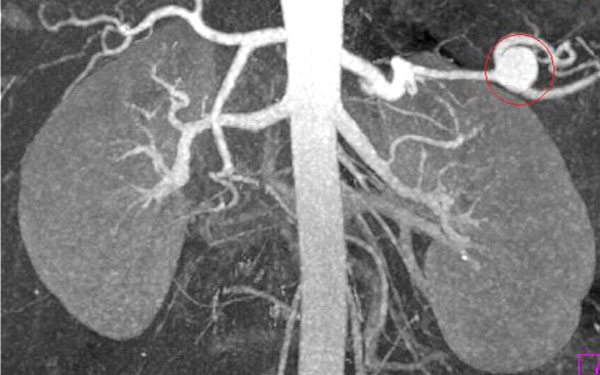

A CT with a contrast of the abdomen showed the abdomen full of blood and the contrast blushed in the area of the splenic artery suggesting a rupture. Thrombocytopenia was noted and she was given two platelet packs as well.

At that point, the physician elected to try the HemaShock®. After rolling one device on each leg, the pressure immediately rose to 100 systolic. The dopamine was turned off and the patient was transferred to interventional radiology, where attempts to plug an aneurysm for two hours were unsuccessful.